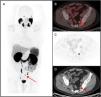

Radiotherapy is a treatment with curative intent, both in patients with primary diagnosis of prostate cancer (PCa) and in patients presenting with biochemical recurrence after radical prostatectomy (RP). Moreover, the use of stereotactic body radiotherapy as a metastasis directed therapy in patients with oligometastatic PCa has significantly increased in the recent years. Conventional imaging techniques, including transrectal ultrasound, computed tomography (CT), morphologic magnetic resonance and bone scintigraphy have traditionally played a minor role in all those clinical scenarios due to its low diagnostic accuracy. The recent development of the positron emission tomography (PET) radiotracer 68Ga-PSMA binding to the prostate specific membrane antigen (PSMA), a transmembrane glycoprotein overexpressed in PCa cells, has shown promising results. Detection rates for PCa lesions are higher than CT and higher than the best technique available, the PET/CT with choline. Its superiority has been demonstrated even at very low PSA levels (<1 ng/ml). This increase in diagnostic accuracy represents a potential impact on patient management, especially in radiotherapy. Even if this imaging technique is already available for routine clinical practice in some European countries, in Spain, unfortunately, there is very limited access. In this review, we analyze the main studies that investigate the usefulness of 68Ga-PSMA PET/CT in patients with PCa and its potential impact on radiotherapy treatments. In addition, we compared the 68Ga-PSMA PET/CT, with the multiparametric magnetic resonance imaging and the PET/CT with choline, in the different clinical scenarios.